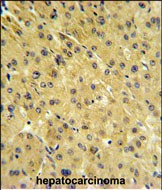

PSMAL Antibody (Center) (Cat. #P32779) IHC analysis in formalin fixed and paraffin embedded hepatocarcinoma followed by peroxidase conjugation of the secondary antibody and DAB staining. This data demonstrates the use of the PSMAL Antibody (Center) for immunohistochemistry. Clinical relevance has not been evaluated.